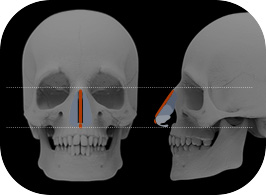

1Check current status

We proceed with 3D-CT imaging to closely analyze the current condition.

2Design and Prediction

We design a nose shape that suits the current state through software.

3Establishment of surgery plan

The surgeon and the patient have an in-depth consultation to establish a surgical plan.

4Custom Nose Implant

A custom-designed, custom-made nose implant for patients is made with a 3D printer.